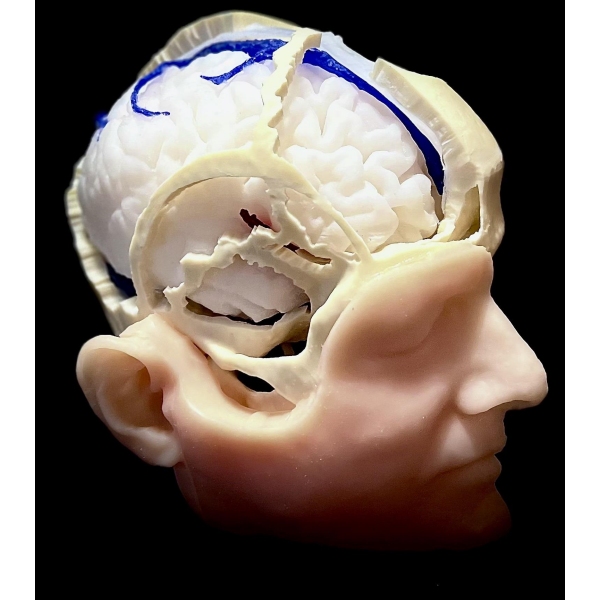

Človeška lobanja z vsemi kraniometričnimi točkami, razpokami in kanali. 1:1, pomanjšano na podlagi resničnega človeškega CT-posnetka na podlagi s podobnimi lastnostmi vrtanja kot človeška kost. Vključuje kožo, intrakranialno možgansko ovojnico, falx, tentorium, venske sinuse in vse lobanjske živce, arterije ter možgane, možganovino in možgansko deblo. Patologija: meningiom olfaktornega žleba, meningiom sfenoidnega krila, parafalcinalni meningiom, trigeminalni švanom in vestibularni švanom. Vse je bilo pridobljeno iz resničnih primerov, vključno s slikami DICOM za predoperativno načrtovanje.